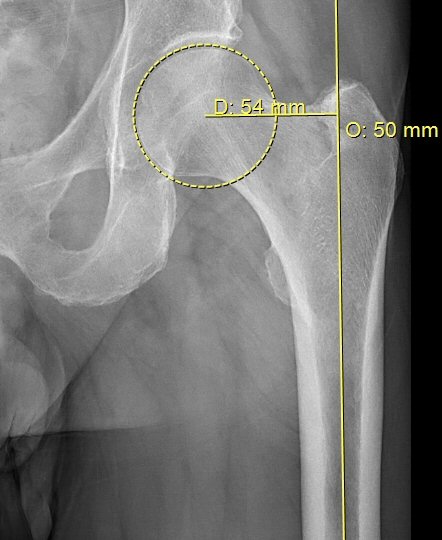

- Mät offset på frisk sida alt. gammal bild. Välj "Offfset" i "Ortho MSK", lägg linje i centrum av femur och kula med centrum i kaputs rotationscentrum. För att få korrekt värde så ska benet vara inåtroterat 15° på röntgenbilden.